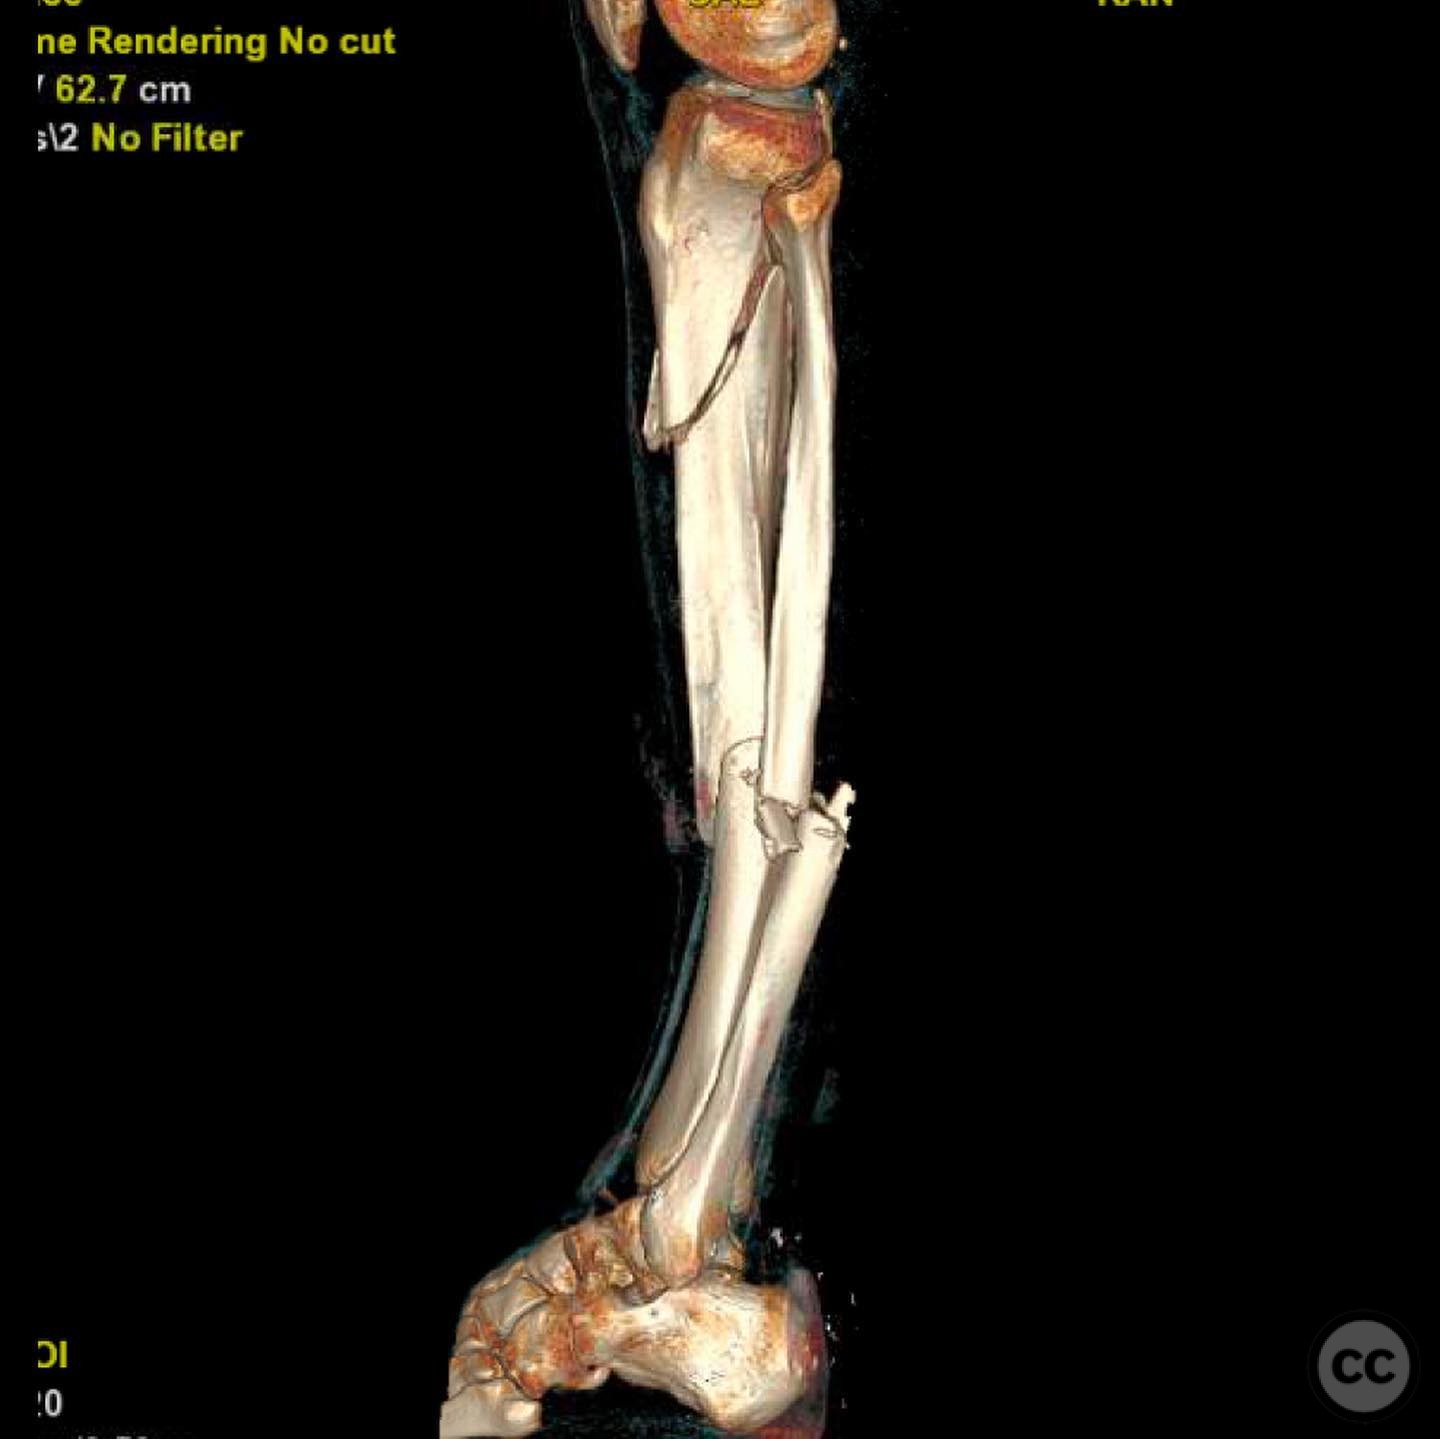

Clinical and radiological findings:  A 44-year-old male cyclist was involved in a collision with a car, resulting in open fractures of the distal femur and segmental tibia. The femoral fracture presented with a 4 cm transverse wound on the anterior aspect, while the tibial fracture had a 2 cm anterolateral wound at the distal site. There were no associated head, chest, or abdominal injuries, and compartment syndrome was not present. Vascular examination was unremarkable.

Planning remarks:  The preoperative plan involved initial debridement and irrigation of both open fractures. The tibia was prioritized for intramedullary nailing, followed by spanning external fixation of the distal femur. Definitive fixation of the distal femur was planned for two days post-initial stabilization.

Anatomical surgical approach:  For the tibia, a longitudinal incision was made to access the proximal tibial start site for intramedullary nailing. Percutaneous clamps were utilized for reduction, supplemented by blocking screws as needed. For the distal femur, an external fixator was applied initially, followed by an in situ lateral approach for plating after reduction was achieved.

The tibial nailing required precise identification of the start site under fluoroscopic guidance, with percutaneous clamps aiding in reduction. Blocking screws were considered but not necessary due to successful reduction with clamps alone. The distal femur presented challenges in achieving coronal and sagittal alignment, necessitating reliance on the external fixator for reduction before proceeding with plating.

Orthopaedic implants used:   Intramedullary nail for tibia, external fixator for initial femoral stabilization, and locking plate for definitive femoral fixation.